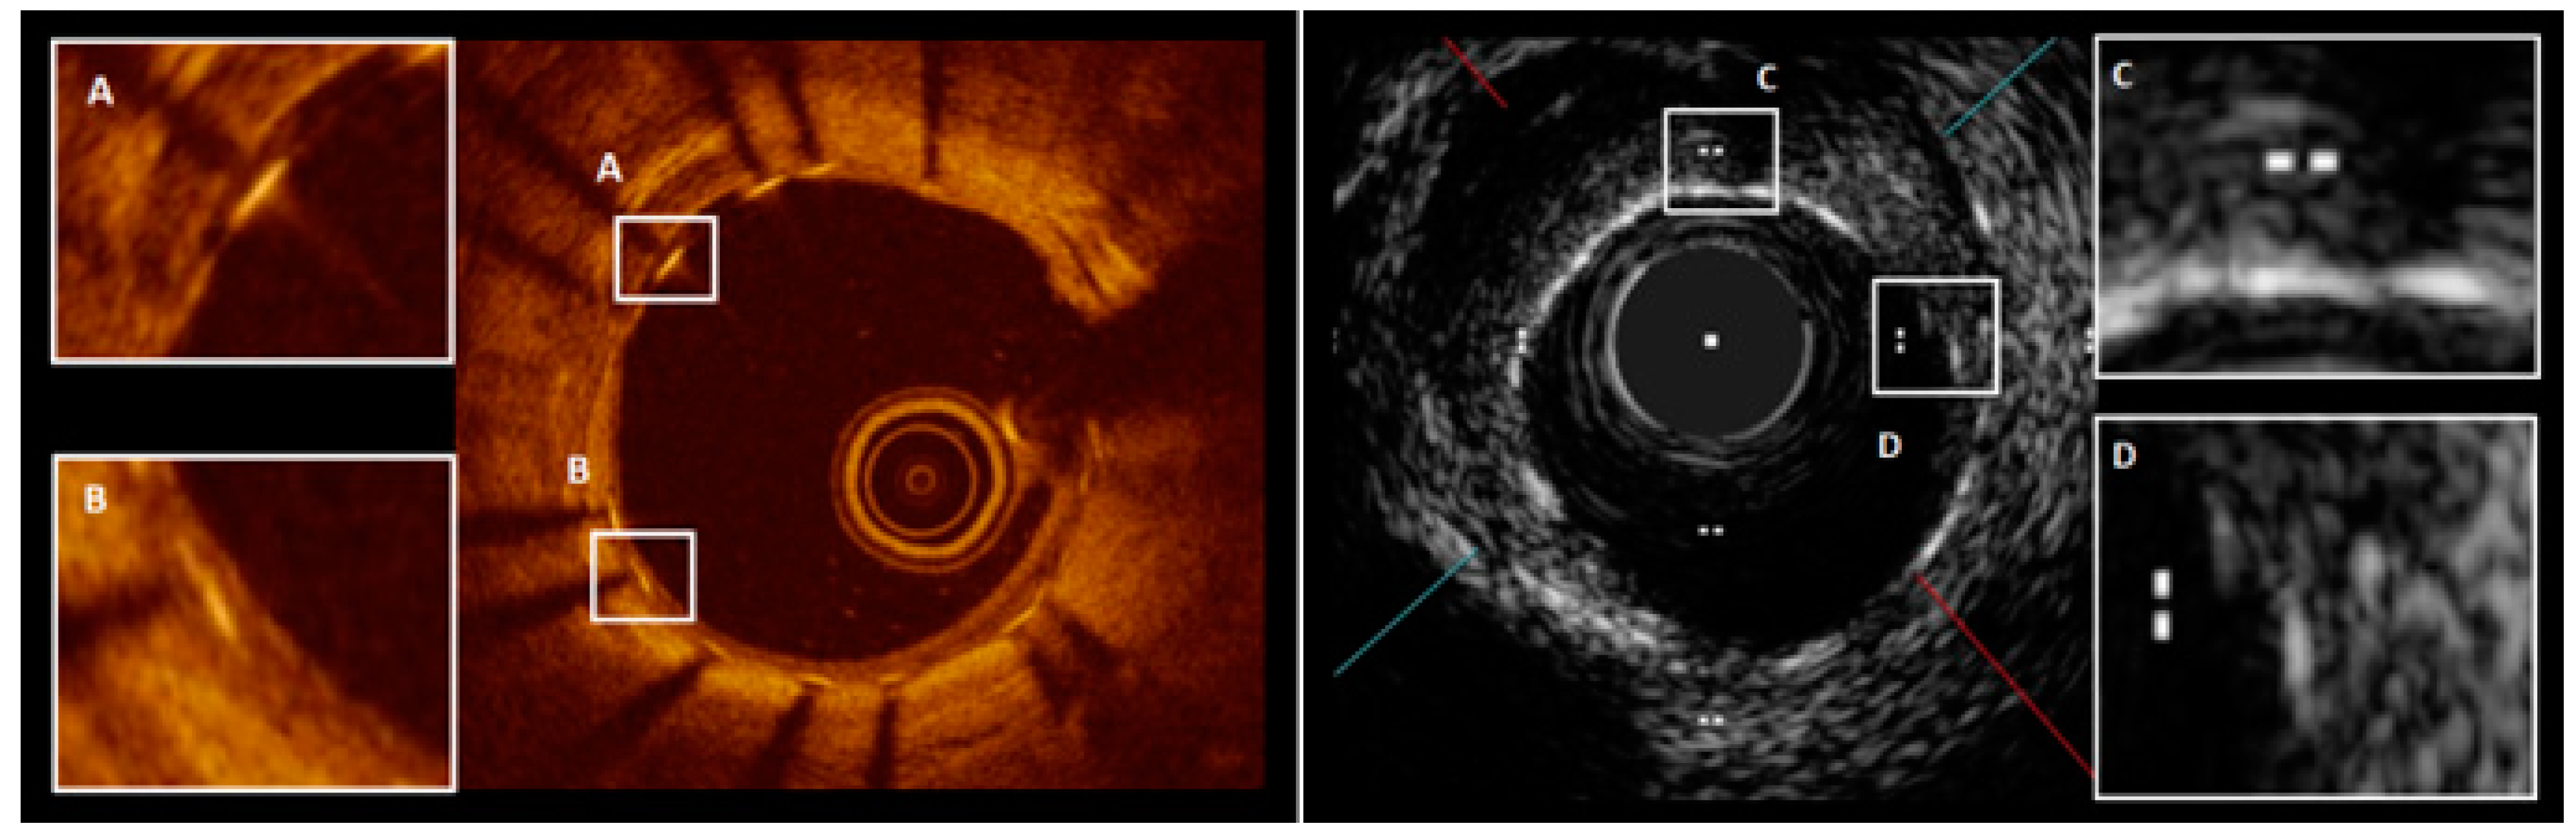

4. Neointimal Coverage Assessed by OCT

Optical Coherence Tomography (OCT) and High-Definition Intravascular Ultrasound (HD-IVUS)